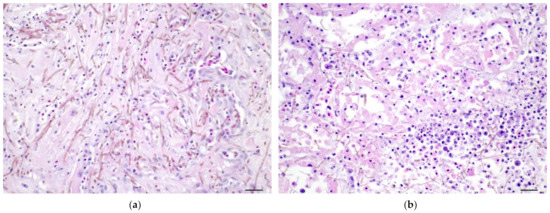

3.3.2. Histopathology